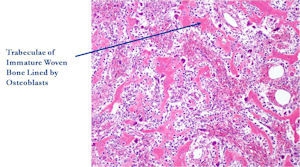

Microscopic Pathology

- Interlacing network of bone trabeculae in a loose fibrovascular stroma

- Prominent vessels

- Osteoblasts are plump, active, scattered mitotic figures

- Osteoblasts line up around periphery of trabeculae (Osteoblastic Rimming)

- Soft tissue component usually surrounded by shell of reactive bone or periosteum (Egg Shell Rim of Calcification)

- No cartilage production (as opposed to osteosarcomas that may contain areas of cartilage)